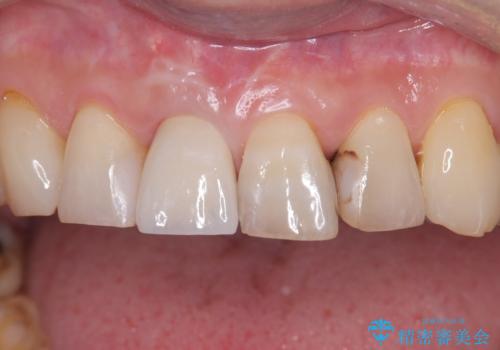

約3か月の治癒期間を経て、最終的にセラミックの上部構造を装着。周囲の歯や歯ぐきとの調和を図りながら、自然な見た目としっかりとした噛み心地を再現しました。患者さんからは「折れて落ち込んでいたが、見た目も噛み心地も元通りで嬉しい」とのお声をいただきました。即時埋入により、精神的な負担も少なく治療を終えることができました。